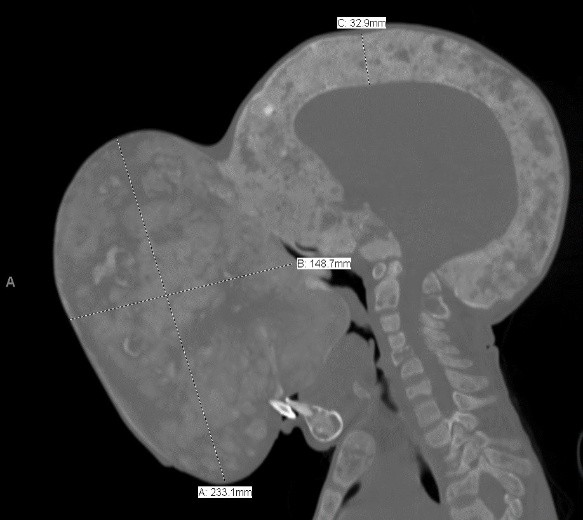

Emanuel Zayras, de Villa Clara, localidad del centro de Cuba, fue operado hace más de una semana en el Holtz Children's Hospital, división pediátrica del centro médico Jackson Memorial, y en donde tras una intervención de 12 horas el equipo de cirujanos logró extirparle el tumor del tamaño de una pelota de básquetbol.

Emanuel Zayras nació con una displasia fibrosa poliostótica, una afección que reemplaza zonas óseas con tejido fibroso.

Este trastorno le afectó en extremidades y en el cráneo desde los 2 años, pero a partir de los 11 un bulto al lado de la nariz empezó a crecer de forma excesiva, lo que dificultaba la respiración y alimentación del menor hasta provocarle una desnutrición extrema.